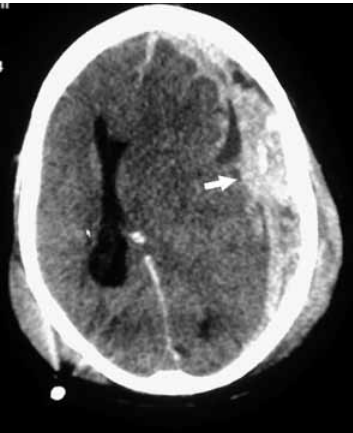

Analise a imagem tomográfica.

O diagnóstico correto é: